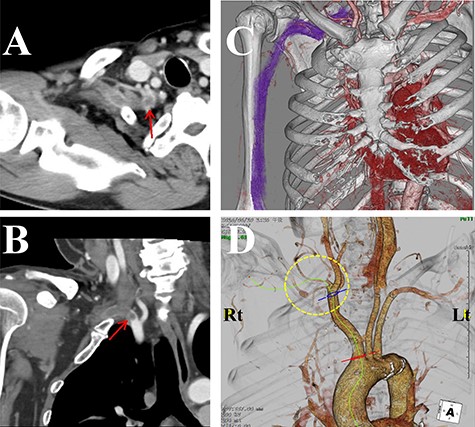

The laboratory data revealed inflammation (white blood cell: 17 500/μl; C-reactive protein: 19.34 mg/dl). Although an increase in D-dimer levels (1.1 ng/ml) was not observed, the contrast-enhanced CT imaging revealed that the subclavian artery was occluded, and a successive distal arterial embolism was produced (Fig. 4). We diagnosed him with an acute arterial occlusion associated with TOS.

Contrast-enhanced computed tomography (CT) images of the thorax. (A) Axial view. (B) Coronal view. (C, D) Three-dimensional CT images. The subclavian artery (circle) was occluded due to a thrombus (arrow) at the level of the dysplasia of ribs.

Three weeks after the onset of right-hand symptoms, he was treated with an emergency thrombectomy. The right subclavian arterial lumen was filled with an organized thrombus. After a few days of anticoagulation therapy (heparin 20 000 U/day) to prevent recurrent or new emboli, the pulse of the right radial artery could be felt, and the gangrene seemed to be reduced. One month after thrombectomy, surgical decompression was performed. After the scalenus anterior/medius muscle was dissected free from the first/second rib using the supraclavicular fossa approach, the high riding first rib was resected with the second rib (Fig. 5).